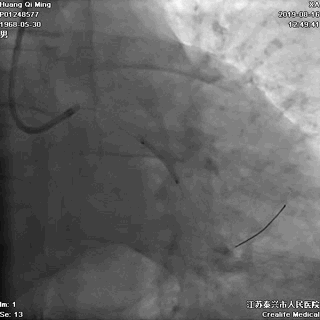

冠状动脉造影

右冠状动脉无严重狭窄

左主干前分叉处血管正常

LCX近中段病变,狭窄最重达90%

LAD中远段血管偏细,弥漫性病变,狭窄达90%

导丝通过病变

球囊扩张,PTCA

支架定位和植入

高压扩张使支架贴壁

LCX植入后即刻效果满意